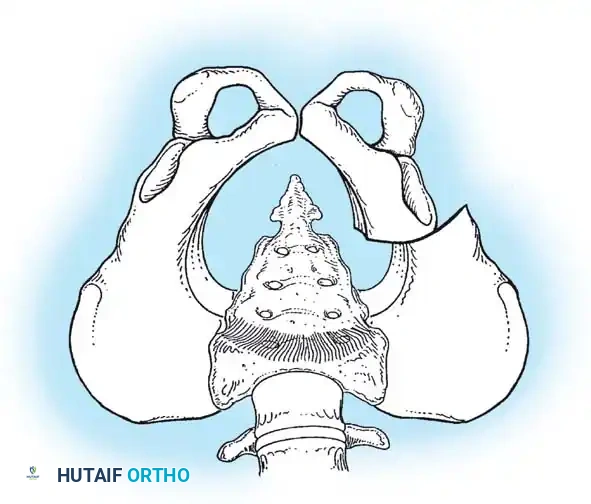

Fig 27-1: Ortolani maneuver for routine screening. The examiner stabilizes the pelvis, places the index and middle fingers over the greater trochanter, and gently abducts the hip.

Surgical Warning: Both tests require a relaxed, pacified child. Forceful maneuvers must be strictly avoided, as they can damage the delicate infantile articular cartilage or cause iatrogenic instability.

Routine clinical screening must include the Ortolani test and the provocative maneuver of Barlow.

* Ortolani Maneuver: Performed by gently abducting and elevating the flexed hip to detect the reduction of a dislocated femoral head into the true acetabulum. A palpable "clunk" indicates a positive test.